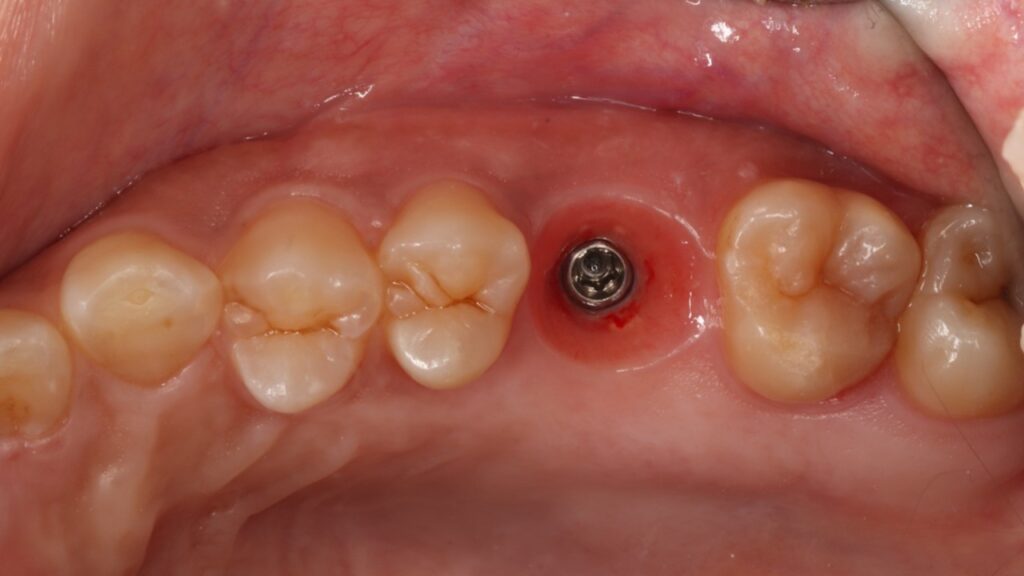

条件によっては即時埋入が出来ないことも多くありますが、もし即時埋入が可能であれば術後の痛みや腫れも少なく、短期間で冠をかぶせることが出来ます。

術後も痛みや腫れはあまりなく順調に経過しました。